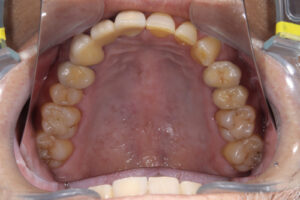

- クリーニングの後、上下顎臼歯部にセラミックインレー・アンレー・インプラントを装着した。

審美的な仕上がりで、患者自身も満足した。3年経過し良好である。

- 現在は2〜3ヶ月おきのメインテナンス中である。